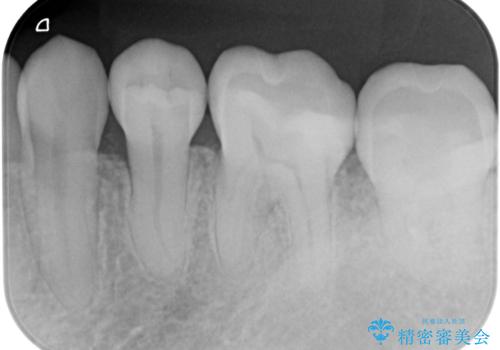

- メタルインレーが取れてしまって来院。

虫歯が再発していたので拡大鏡下で取り切った後、e-maxインレーにて治療しました。

また、一番奥の歯も古い樹脂の治療がされていたため虫歯の予防のために樹脂を取り除き、う蝕がないことを確認してe-maxインレーで治療しました。

樹脂(プラスチック)の治療は白くて審美性は良いが経年的に劣化します。

た歯質との隙間ができてしまうため虫歯の再発のリスクが高いです。

e-max(セラミック)は歯質との隙間が出来にくく虫歯の再発のリスクが低くなります。